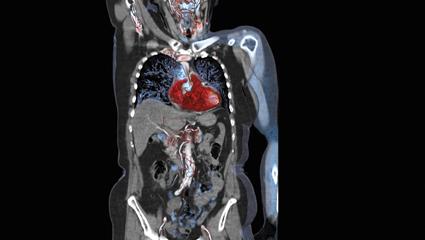

Newly unveiled at RSNA 2013 and 510(k)-pending, the IQon Spectral CT from Philips attempts such differentiation using a single imaging chain to capture X-rays at different wavelengths. Colors identify the composition of structures. Cancer appears bright red due to a concentration of iodinated contrast medium in the vascular bed feeding a tumor. A pulmonary embolism appears in blue due to a lack of vasculature. Conventional gray scale images show the underlying anatomy.